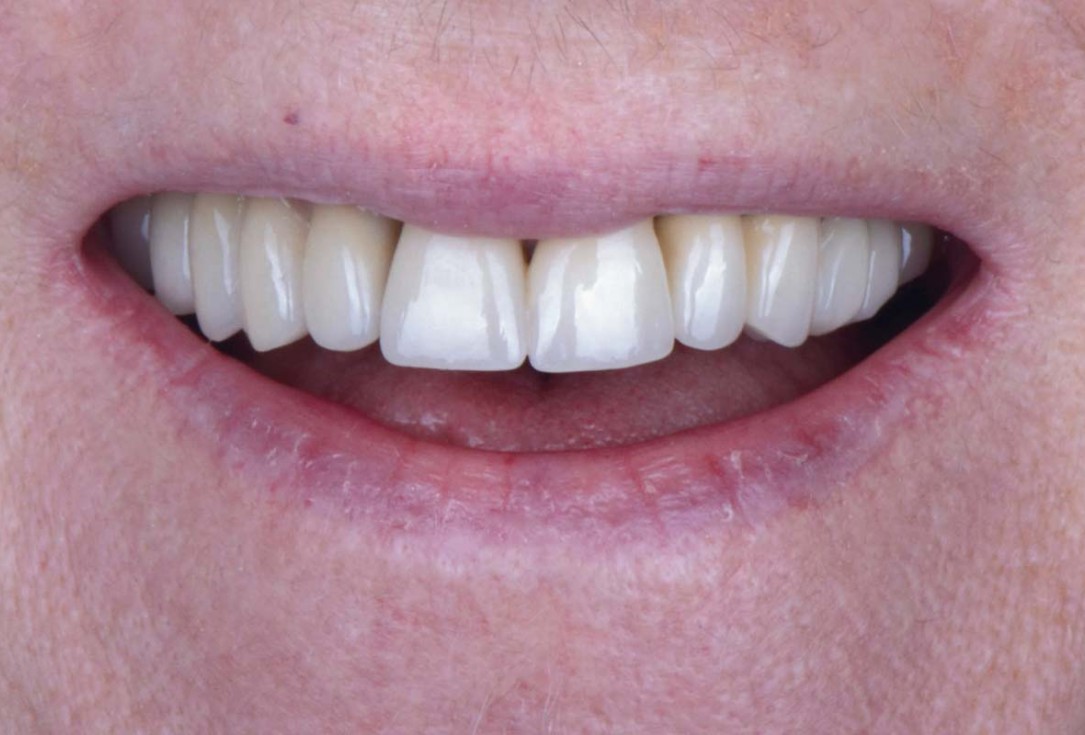

Smile rehabilitation in the anterior maxilla with maxgraft® bonebuilder - Dres. A. Dagba and J. Mourlaas